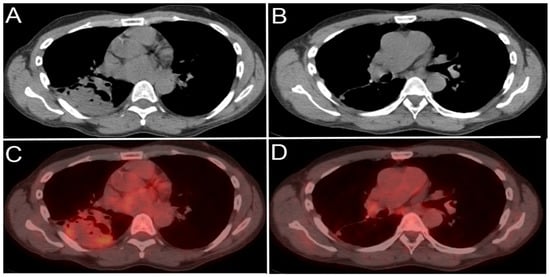

4.1.3. Positron Emission Tomography (PET) and Positron Emission Tomography-Computed Tomography (PET-CT)

- Riegger, C.; Koeninger, A.; Hartung, V.; Otterbach, F.; Kimmig, R.; Forsting, M.; Bockisch, A.; Antoch, G.; Heusner, T.A. Comparison of the Diagnostic Value of FDG-PET/CT and Axillary Ultrasound for the Detection of Lymph Node Metastases in Breast Cancer Patients. Acta Radiol. 2012, 53, 1092–1098. [Google Scholar] [CrossRef] [PubMed]

- Cochet, A.; Dygai-Cochet, I.; Riedinger, J.-M.; Humbert, O.; Berriolo-Riedinger, A.; Toubeau, M.; Guiu, S.; Coutant, C.; Coudert, B.; Fumoleau, P.; et al. 18F-FDG PET/CT provides powerful prognostic stratification in the primary staging of large breast cancer when compared with conventional explorations. Eur. J. Nucl. Med. Mol. Imaging 2014, 41, 428–437. [Google Scholar] [CrossRef]